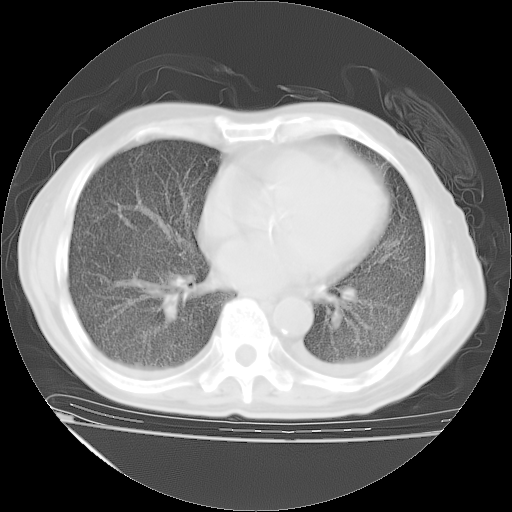

经过24天治疗,岳父的病情基本稳定。生活基本可以自理,可以下床活动。呼吸困难早已消失。体温基本正常。

只是甲强龙用80mg时血小板升到正常,改为60mg后又降到63×10*9/L。

主要治疗甲强龙80mg×14天,60mg×10天;同时抗结核(异烟肼+利福平+乙胺丁醇)。环磷酰胺0.1 tid 10天。

特别感谢胡教授、高管、桃子版主给出关键的治疗建议。桃版把所有肺部影像和全部临床资料请所在医院呼吸科、感染病科、结核科、临床免疫科专家会诊。临床免疫科专家制定了完整的治疗方案。